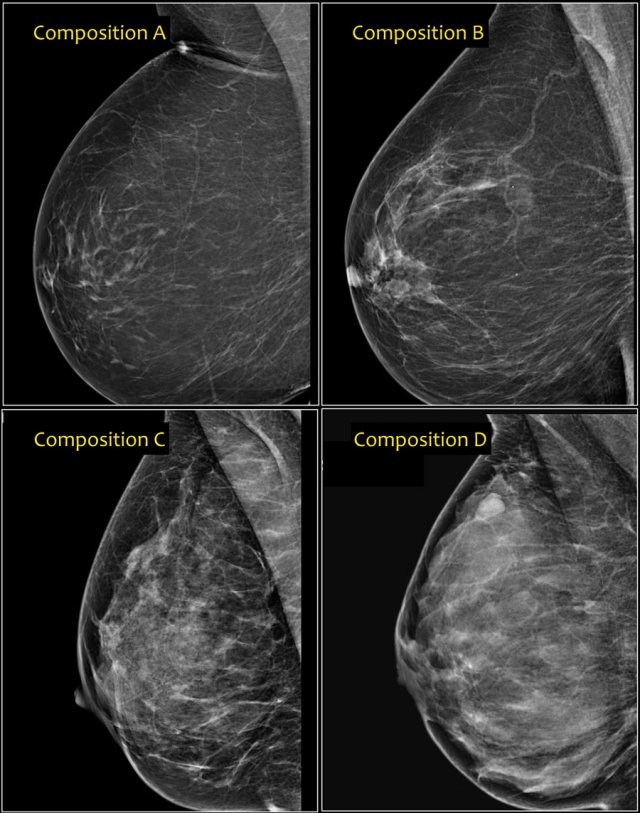

الصواب والخطأ حول الصورة الشعاعية للثدي

الصورة الشعاعية للثدي هي الوسيلة الأساسية للكشف المبكر عن سرطان الثدي الذي هو أول السرطانات التي تصيب المرأة بمعدل امرأة من كل 8. رغم ذلك، لا تزال تحيط بها أفكار عديدة خاطئة ونسبة مهمة من النساء لديهن هواجس بشأنها ما يجعلهن مترددات بشأن اللجوء إليها، وفق ما نُشر في Webmd.

- الصورة الشعاعية الثلاثية الأبعاد مماثلة لتلك التقليدية: تُعدّ الصورة الشعاعية الثلاثية الأبعاد أحدث الوسائل الحديثة للكشف المبكر عن سرطان الثدي. هي تكشف المزيد من التفاصيل وتصل إلى أقسام رقيقة جداً في أنسجة الثدي.